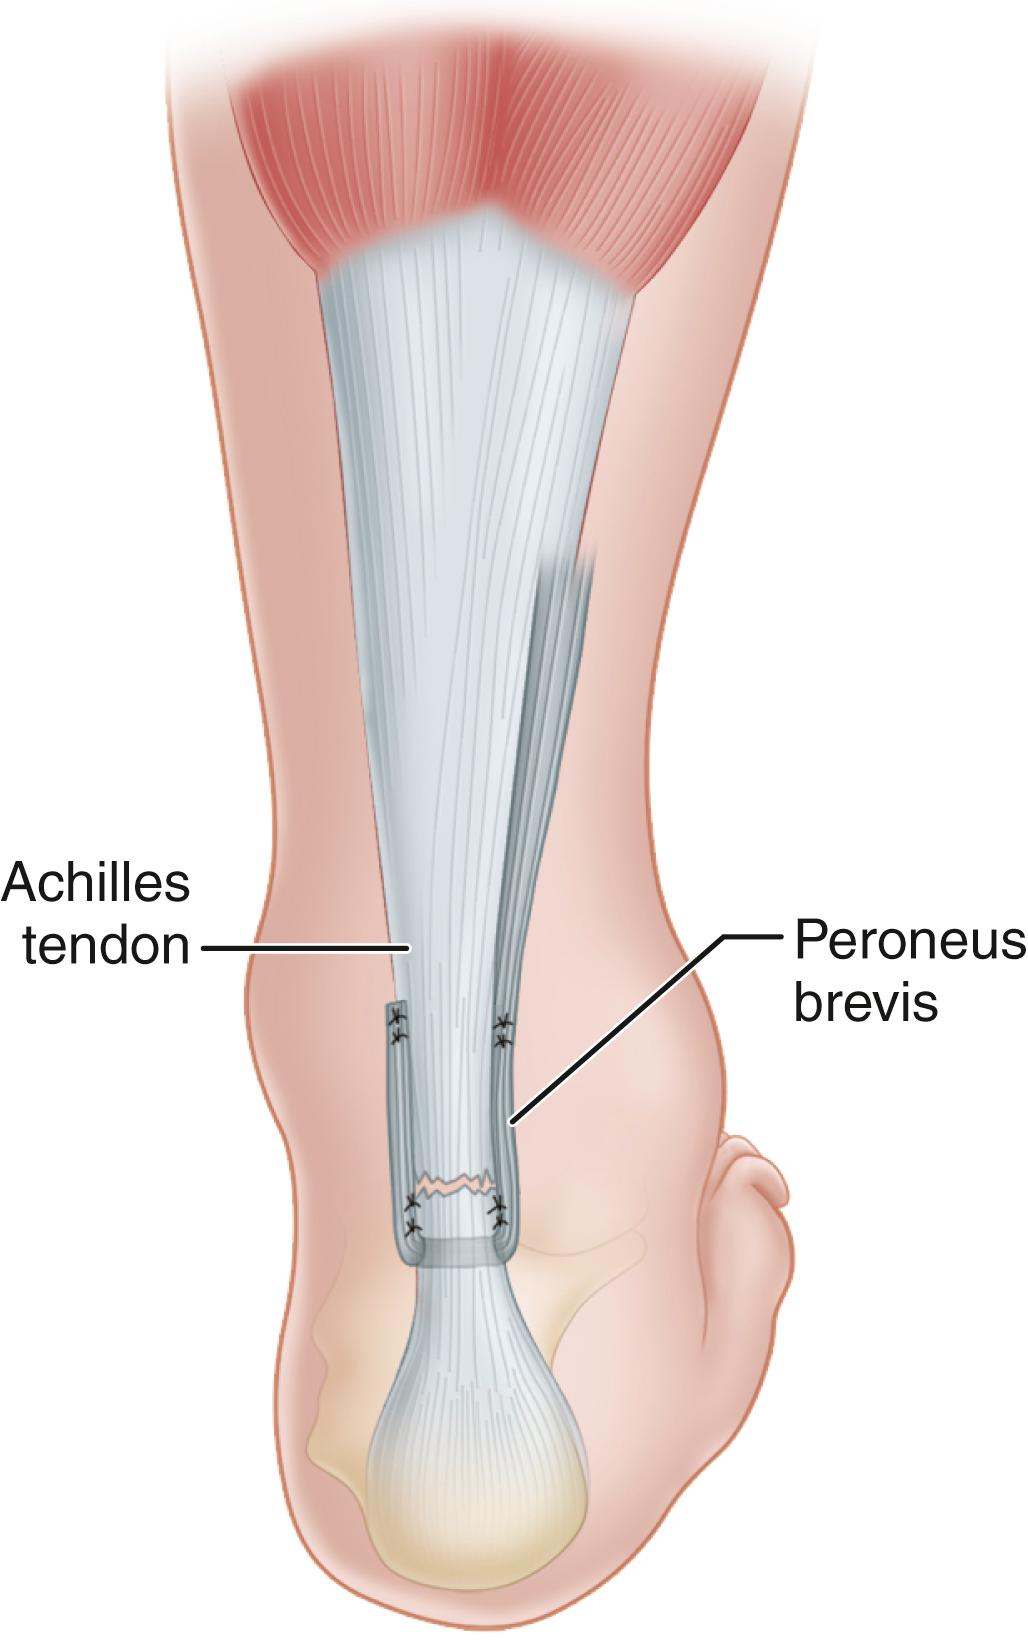

• Pass the peroneus brevis tendon through this hole and back proximally beside the Achilles tendon, reinforcing the site of rupture, and suture it to the peroneus brevis itself, producing a dynamic loop ( Fig. 48.19 ).

FIGURE 48.19, Dynamic loop suture of peroneus brevis to itself when end-to-end suture is not possible. SEE TECHNIQUE 48.11 .

Turco and Spinella described a modification in which the peroneus brevis is passed through a midcoronal slit in the distal stump of the Achilles tendon. The graft is sutured medially and laterally to the stump and proximally to the tendon with multiple interrupted sutures to prevent splitting of the distal tendon stump ( Fig. 48.20 ). This modification can be beneficial if a long distal stump is present.

FIGURE 48.20, Turco and Spinella modification. Peroneus brevis is passed through midcoronal slit in distal stump of Achilles tendon and sutured to stump and to tendon. SEE TECHNIQUE 48.11 .